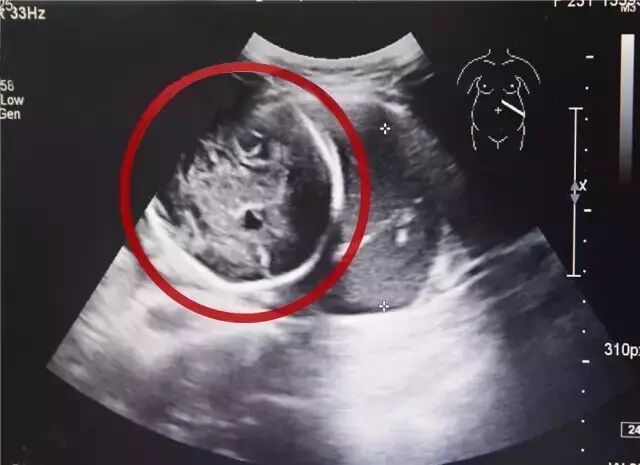

4月12日傍晚,海宁市一家医院接诊了一位极其罕见的孕妇。这名孕妇怀胎6个多月,子宫里居然是空的!

经B超检查,小芳竟然已经怀孕了,而且胎儿已经长到了6个多月!但是让人震惊的是胎儿并没有长在子宫里,而是长在了腹腔内。经过确诊,小芳为“腹腔妊娠”,是宫外孕的一种,这种发病率约为1:15000,母体死亡率约为5%,胎儿存活率仅为1%的罕见妊娠!